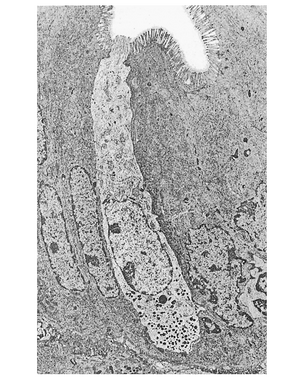

[[文件:BL-27.5.png|缩略图|• 图27.5 胃肠道开放型内分泌细胞的电镜照片。注意顶端的微绒毛和基底外侧部的分泌颗粒。]] | |||

肠内分泌细胞富含分泌颗粒,其内容物在胃肠道壁受到化学或机械刺激时释放(图27.5)。此外,肠内分泌细胞也可被神经输入或与摄食无关的其他因素激活。肠壁中最常见的肠内分泌细胞属于'''"开放型"'''(open type),<u>这类细胞的顶膜与肠腔接触(通常为感受刺激的部位),基底外侧膜负责分泌</u>。另存在'''"闭合型"'''(closed type)肠内分泌细胞,<u>其细胞膜不与肠腔表面接触,例如胃上皮中分泌组胺的肠嗜铬样细胞</u>(enterochromaffin-like cell,ECL cell)。 | |||